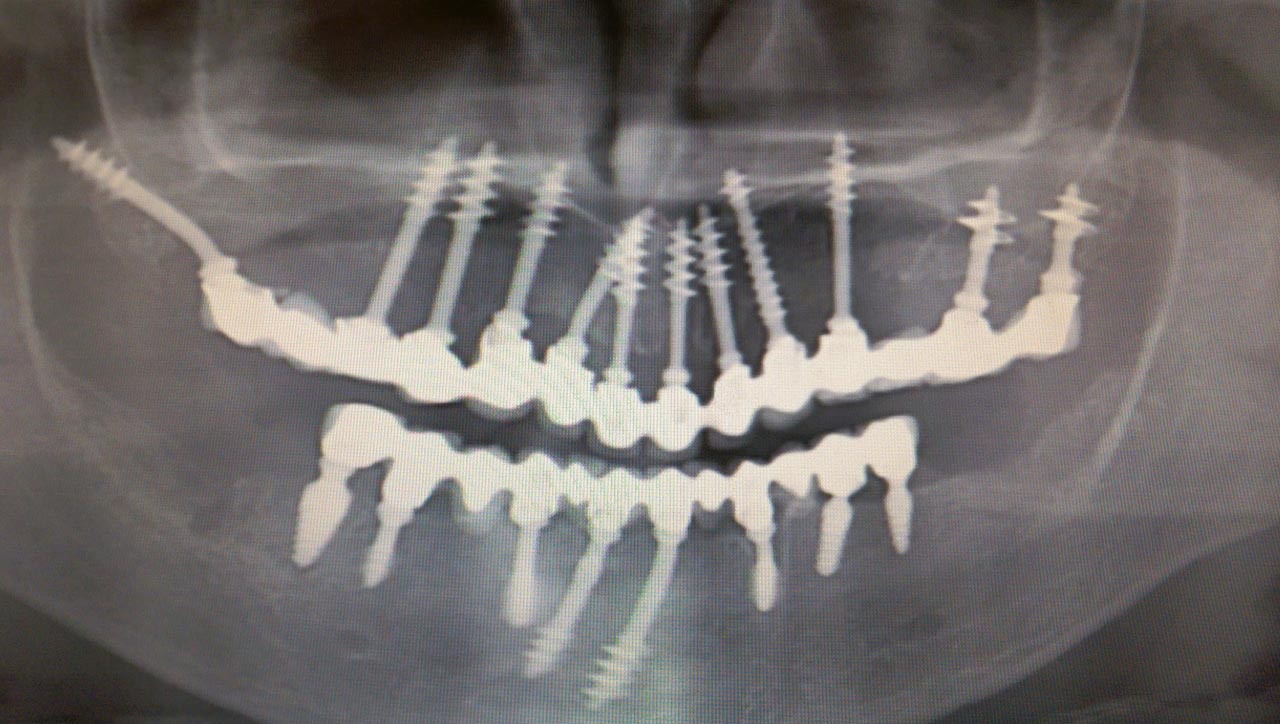

Elhanyagolt fogsor cseréje 2 nap alatt

2 nap alatt varázsoltuk ezt a szép esztétikus alsó, felső körhídat implantátumokkal megtámasztva a korábban elhanyagolt szájba. Az 1. nap 26 fogat távolítottunk el, mert annyira rossz állapotban voltak, és rögtön azonnal terhelhető IHDE svájci implantátumokat raktunk be, fentre 8, lentre 6 darabot. A sebeket összevarrtuk és intraorális szkennerrel digitális lenyomatot vettünk. 2 nap múlva pedig beragasztottuk a kész PMMA műanyag körhidakat. Dr. Kelemen Péter és a Symbion Fogtechnika munkája.